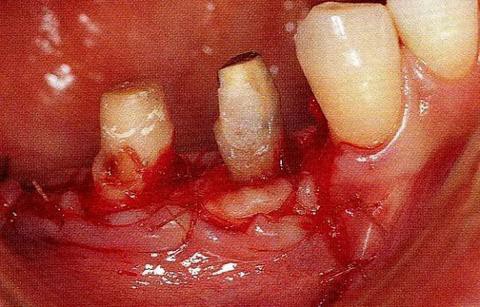

圖17-4(左),5 (右)  術(shù)后9年的口腔內(nèi)照片和X線片,牙槽嵴平坦化,牙周探診數(shù)值很小。